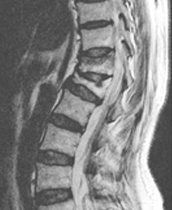

압박골절

눌리는 힘(압박력) 때문에 척추뼈에 골절이 생기는 질환

경추(목뼈)와 요추(허리)에 자주 발생하며 뼈속의 칼슘이 빠지면서 척추뼈가 약해져 가벼운 충격(삐끗하거나 넘어질 경우)으로도 척추뼈가 눌리는 골절이 발생할 수 있습니다. 위와 같은 충격을 받은 경우, 원통 모양으로 쌓여져 있는 척추의 뼈가 눌리듯이 골절이 일어나게 되며, 여자가 남자보다 약 3배정도 많습니다.

• 척추체압박골절 척추 전방전위증 이미지